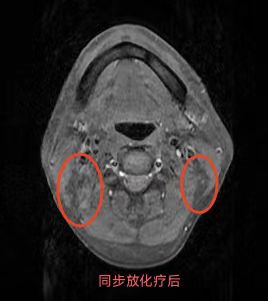

同步放化療(鼻咽癌伴頸部淋巴結(jié)轉(zhuǎn)移)